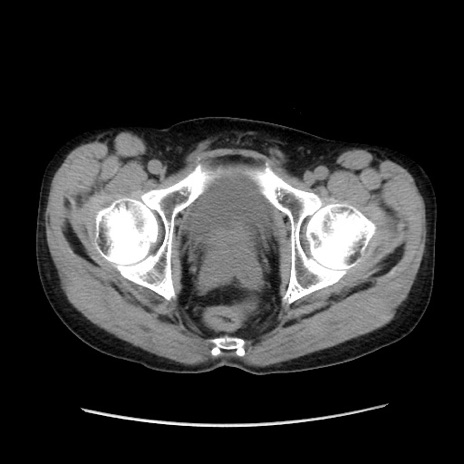

症例37(横断像)

冠状断像

【症例】40歳代 男性

【主訴】腹痛

【現病歴】4時間ほど前に電車に乗車中に臍部上より腹痛出現。徐々に増悪し起立困難となり、救急外来受診。生ものは数日食べていない。今朝お雑煮を食べた。

【身体所見】BT 36.8℃、BP 117/84mmHg、HR 91/min、SpO2 97%、苦悶様、腹部:臍上部広範囲圧痛あり、反跳痛±

【データ】WBC 8100、CRP 0.03